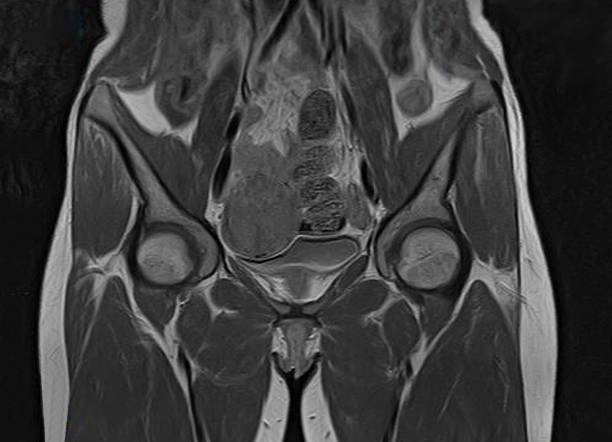

자궁근종(Uterine fibroids)은 여성의 자궁 내에 발생하는 양성 종양으로, 자궁 내막이나 근층에서 생길 수 있습니다. 대부분의 경우, 이 종양은 악성 종양이 아니며, 치료하지 않아도 괜찮은 경우가 많습니다. 그러나 증상이 심한 경우, 치료가 필요할 수 있습니다. 자궁근종의 증상은 그 크기와 위치에 따라 다릅니다. 아무런 증상이 없는 경우도 있지만, 대개는 다음과 같은 증상을 보일 수 있습니다.

위와 같은 증상이 나타날 경우 의사와 상담하여 적절한 치료 방법을 선택해야 합니다. 치료 방법은 자궁근종의 크기, 위치, 증상 등에 따라 달라질 수 있으며, 대개의 경우 증상 완화와 근종 크기 축소를 위해 치료를 시도합니다.

자궁근종의 치료 방법으로는 약물 치료, 수술, 비침습적 절제술 등이 있습니다. 약물 치료는 자궁근종의 크기를 축소시키는 목적으로 사용되며, 경구 투여나 주사 등으로 적용될 수 있습니다. 수술은 자궁근종을 제거하는 수술로 대개 자궁 축소술이나 자궁적출술 등이 사용됩니다. 비침습적 절제술은 자궁근종의 혈액 공급을 차단하여 근종 크기 축소를 유도하는 방법으로, 자궁동맥동결술, 초음파 유도하 고강도 집속초음파(자궁동맥소작술), 대동맥 삽입술 등이 사용됩니다.